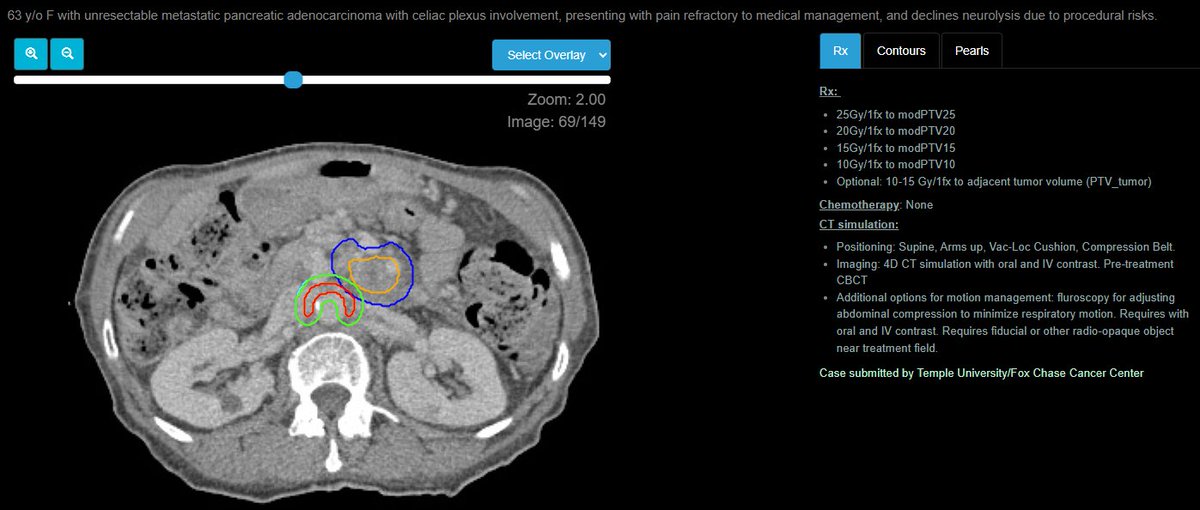

Review your pancreas "Triangle Volume" with this great case, submitted by Serena Moa, MD, PhD from @JohnsHopkins w/ special shout-out to @MikeChuongMD for reviewing! PS: don't forget to check out the dose constraints for this SBRT case! econtour.org/cases/168

eContourRadOnc's tweet image. Review your pancreas "Triangle Volume" with this great case, submitted by Serena Moa, MD, PhD from @JohnsHopkins w/ special shout-out to @MikeChuongMD for reviewing!

PS: don't forget to check out the dose constraints for this SBRT case!

econtour.org/cases/168